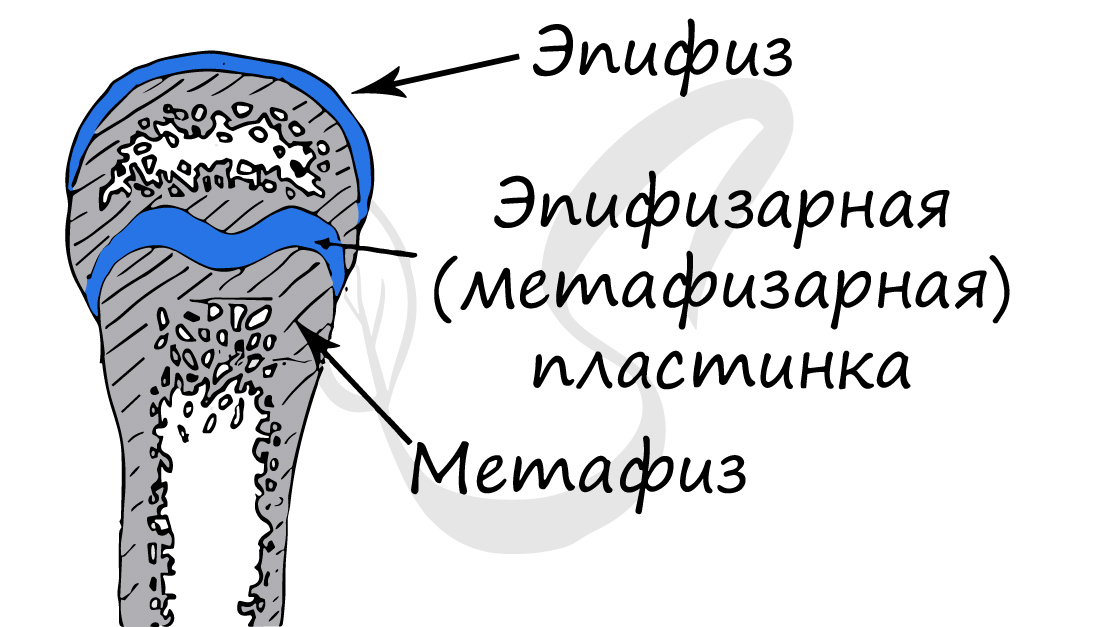

Кость состоит из костного вещества, костного мозга и надкостницы, а также имеет разветвленную сеть кровеносных сосудов и нервов, как показано на рисунке. Длинная бедренная кость состоит из диафиза и двух выпуклых эпифизарных концов. Поверхность каждого эпифизарного конца покрыта хрящом и образует гладкую суставную поверхность. Коэффициент трения в пространстве между хрящами в месте соединения сустава очень мал, он может быть ниже 0.0026. Это самый низкий известный показатель силы трения между твердыми телами, что позволяет хрящу и соседним костным тканям создать высокоэффективный сустав. Эпифизарная пластинка образована из кальцинированного хряща, соединенного с хрящом. Диафиз представляет собой полую кость, стенки которой образованы из плотной кости, которая является довольно толстой по всей ее длине и постепенно утончающейся к краям.

Обратите свое особое внимание на то, что рост кости в длину осуществляется за счет эпифизарной пластинки. Именно за счет этой пластинки, располагающейся между метафизом и эпифизом, происходит рост кости в длину. Эпифизарная пластинка хорошо кровоснабжается.

Трубчатые кости, соответствуя своему названию, представляют собой продолговатое тело или диафиз и два утолщения на концах, эпифизы. Между эпифизом и диафизами расположены метафизы — зоны роста кости в длину. Метафизы постепенно заканчивают свою деятельность и постепенно окостеневают к возрасту полового созревания, когда рост тела в высоту останавливается. Этот период соответствует примерно 18 годам у девушек и 25 годам у парней. В современном мире существует понятие костного возраста, или истинного возраста, тела, в противовес календарному возрасту. Он определяется на основании стадии окостенения метафизов.